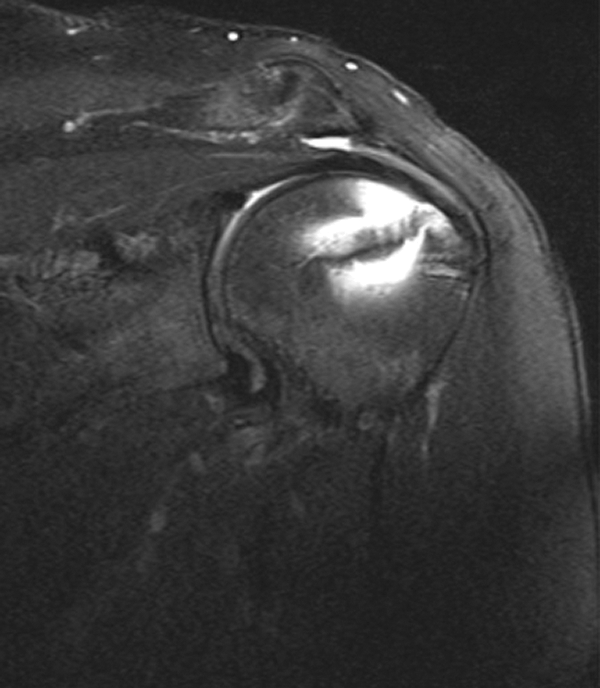

The patients were evaluated with MRI at a minimum of 12 months after surgery for tendon integrity. Postoperative MRI was performed with a 1.5-T Avanto scanner (Siemans AG). Postoperative MRI was evaluated for repair healing (Figures 6 and 7). Anatomic assessment of tendon healing was performed by a shoulder surgeon who did not perform the surgical procedures (P.N.C.), using the grading scale described by Sugaya et al. 14 Grades I through III were considered healed, while grades IV and V were considered unhealed. MRI was also evaluated for retear patterns as defined by Cho et al. 5 Cases were divided into type 1 retears if there was no remaining cuff tissue at the insertion site of the rotator cuff on the greater tuberosity or type 2 retears if a remnant of cuff tissue remained at the insertion site despite the retear.

This postoperative magnetic resonance coronal T2-weighted image demonstrates an intact repair.

This postoperative magnetic resonance coronal T2-weighted image demonstrates a repair that is not intact.